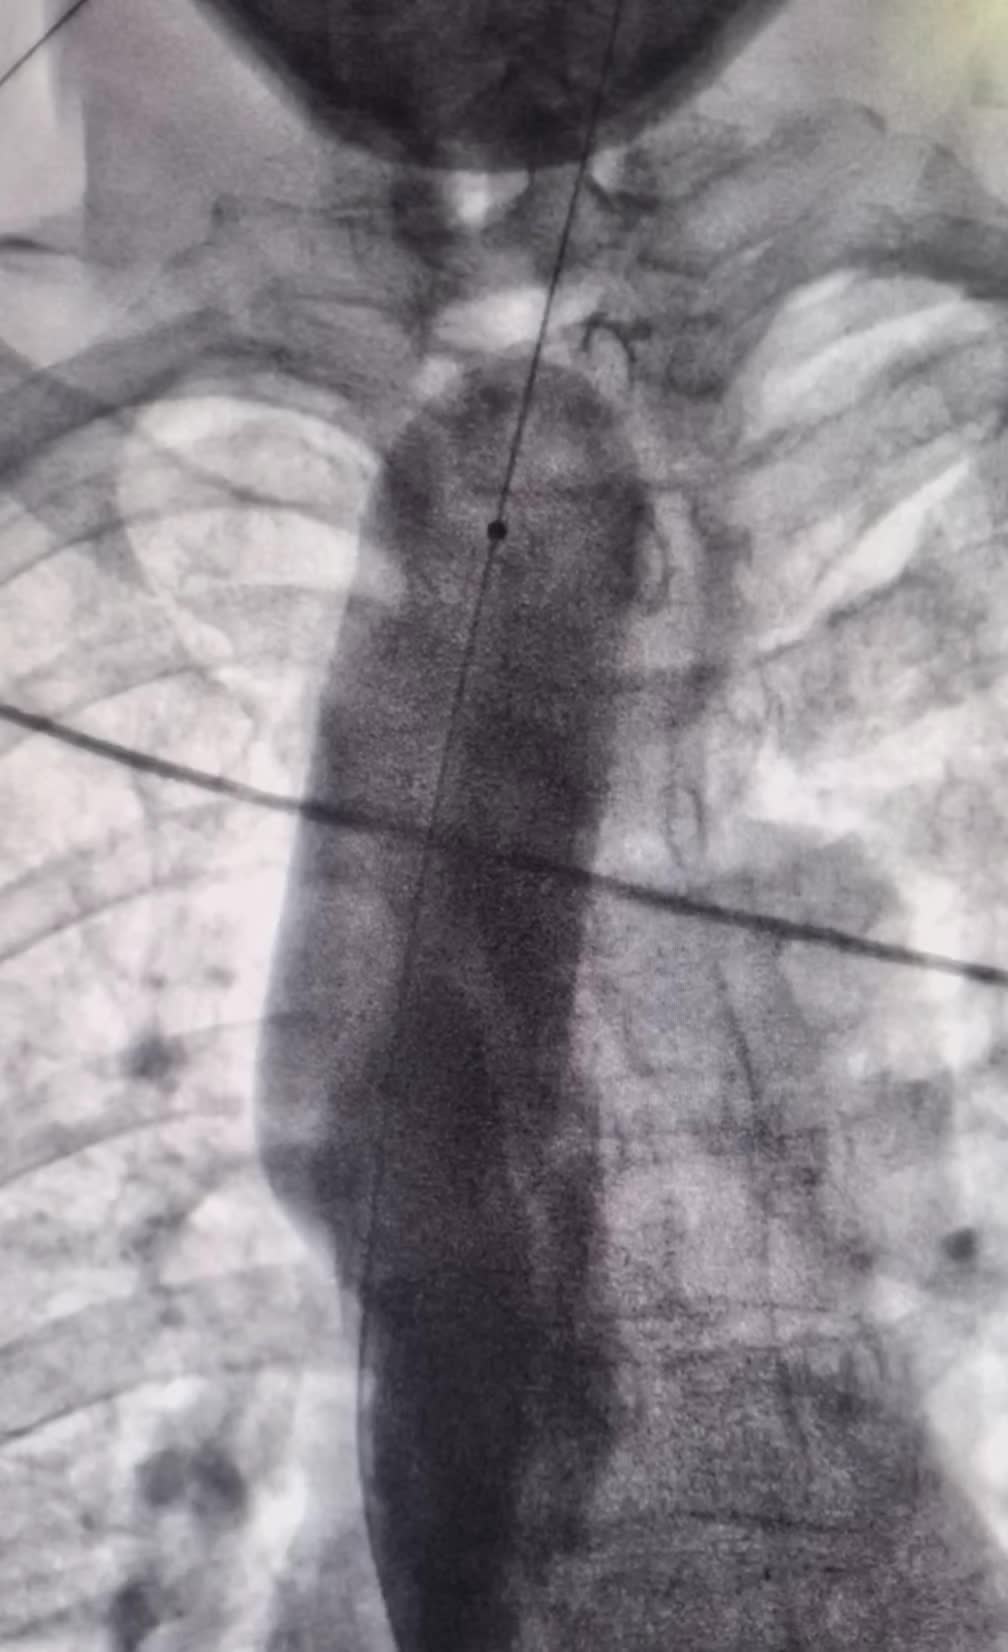

上午一台食管癌术后吻合口狭窄球囊扩张成型 上午一台食管癌术后吻合口狭窄球囊扩张成型术。术后即可恢复正常饮食。